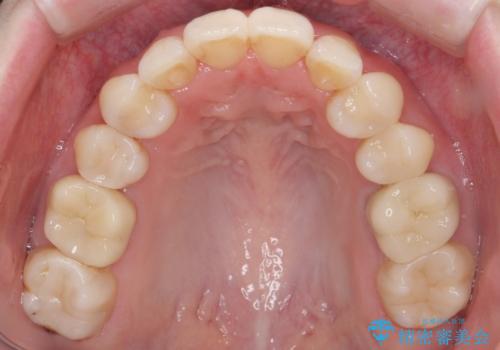

矯正治療後にしっかり全体の虫歯治療も行い、とても良い状態にできたと思います。

犬歯を抜いたとしても、矯正治療を短期間で終わらせて歯に負担がかからないようにし、虫歯治療その分しっかり行うのもメリットがあるのではないかと思います。

今回は特に左上の犬歯は歯肉退縮して根が露出していたのもあり、抜歯をお勧めしました。